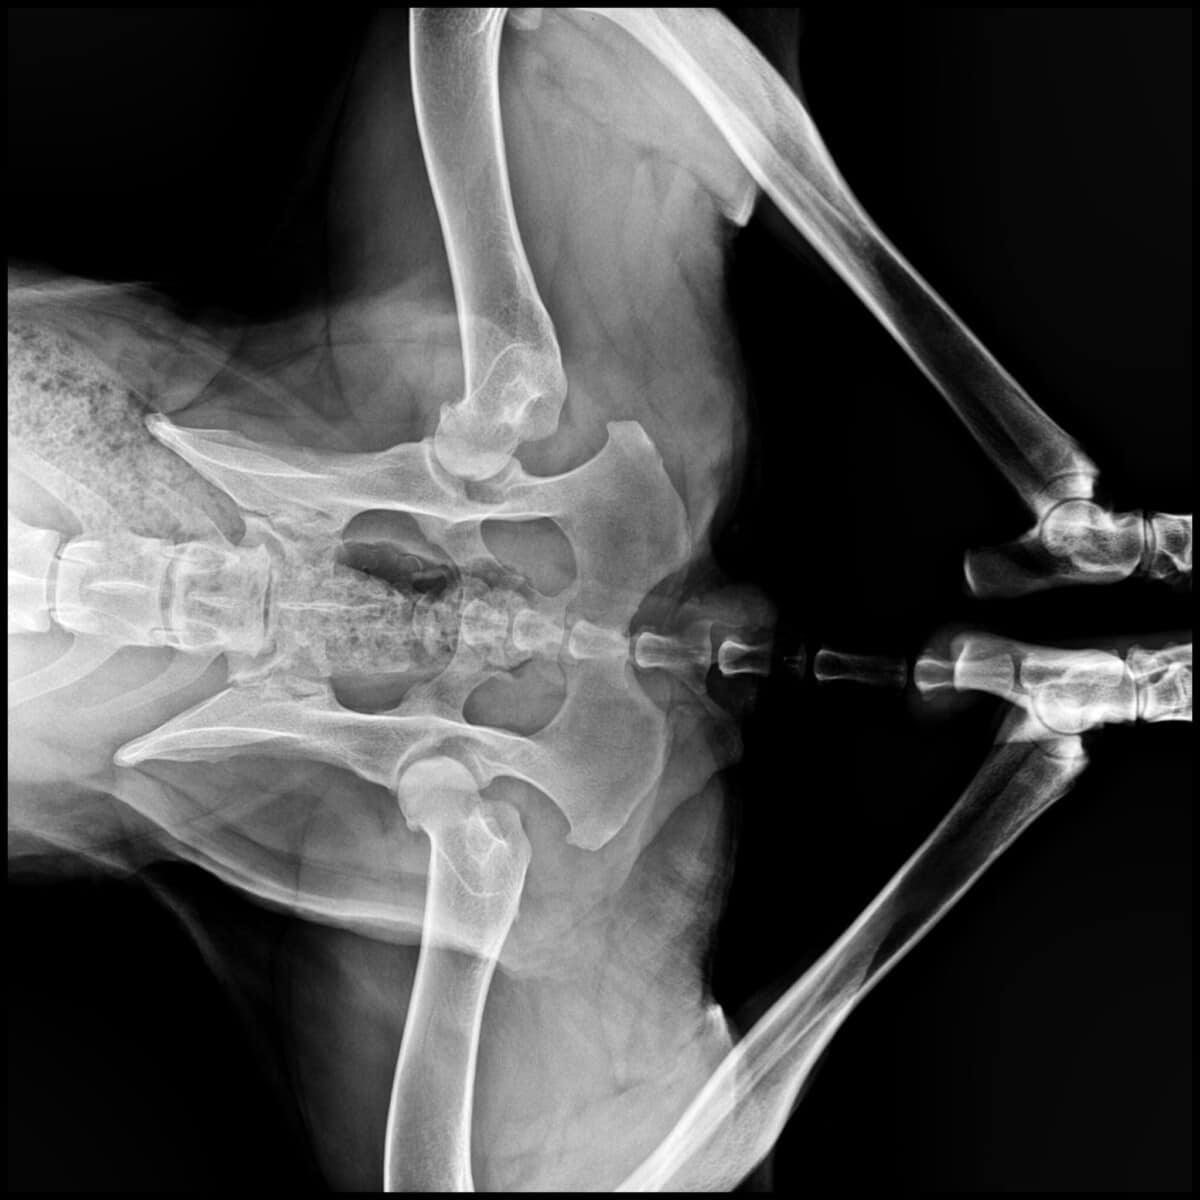

Olen iloinen, aktiivinen ja rakastan kaikkia ihmisiä! Mutta tarhalla huomasivat, että kävelen takajaloillani oudosti. Kun minut vietiin tutkittavaksi, eläinlääkäri antoi ikävän uutisen: minulla on vaikea-asteinen lonkkadysplasia molemmissa lonkissani.